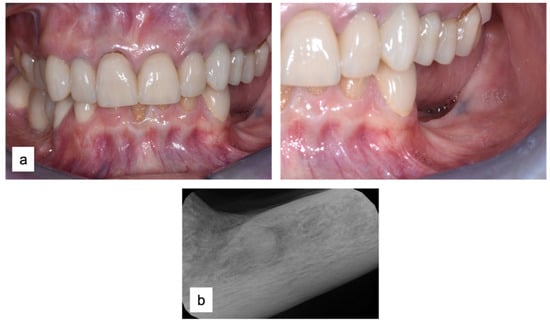

Two implants (Institute Straumann, Basel, Switzerland) of 4 × 12 mm and 5 × 8 mm were inserted in the 3.4 and 3.6 areas, respectively (Figure 9a). The final prosthesis was manufactured with a digital workflow and delivered after three months. The patient was monitored with clinical and radiographic evaluations 12 and 18 months after prosthetic loading. The clinical examination and the digital scans at 12 months of follow-up proved the efficacy of the regenerative approach (Figure 10 and Figure 11). The comparison between 12 (Figure 9b) and 18 month (Figure 9c) radiographs showed stability of the bone crest around the dental implants. Furthermore, a progressive mineralization of the regenerated area was also evident (Figure 9a–c).

Figure 10.

Clinical evaluation after 18 months of prosthetic loading.

Figure 11.

Scan taken after 18 months of prosthetic loading.